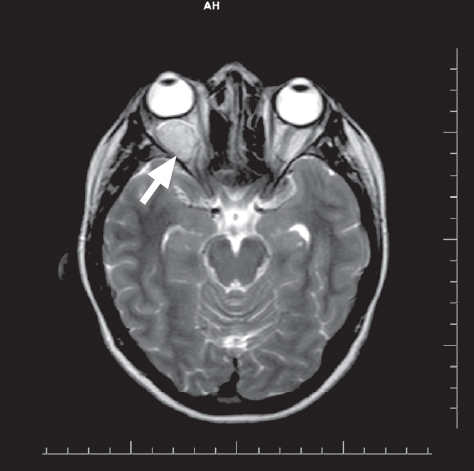

Рис. 3. Магнитно-резонансная томография. Кавернозная венозная мальформация, локализующаяся только в орбите, аксиальная проекция, режим Т2

Fig. 3. Magnetic resonance tomography. Cavernous venous malformation localized only in the orbit, axial view, T2 mode